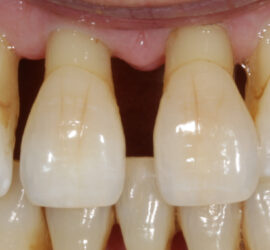

Лечение пульпита. При лечении пульпита перед врачом встают следующие задачи: избавление больного от болевых ощущений, ликвидация инфекционно-токсического очага в пульпе зуба, восстановление формы и функции зуба. Первую помощь больному острым пульпитом может оказать средний медработник или врач любого другого профиля. Она заключается в назначении внутрь обезболивающих препаратов типа анальгина, амидопирина, […]